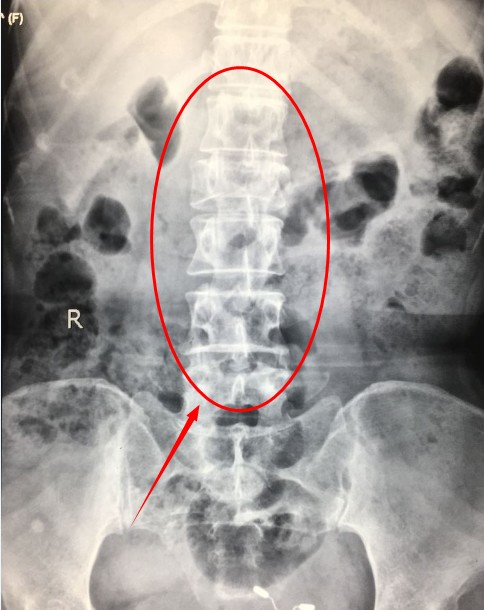

受伤后,司机立即将周女士送往宜宾民心创伤骨科医院接受治疗。以为乘客已经全部医院检查结果显示,周女士腰2椎体爆裂性骨折。

入院不久,在宜宾民心创伤骨科医院骨科主任带领下,医护团队为周女士行“腰2椎爆裂性骨折切开复位钉棒系统内固定术”经过2小时,手术顺利结束。